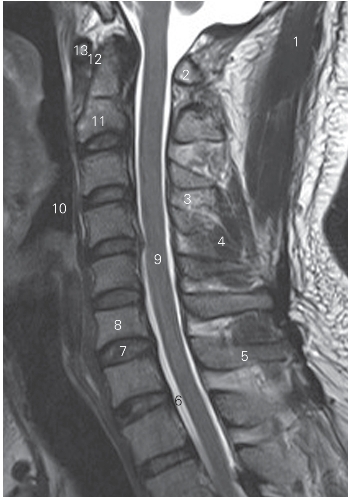

图1-5 经脊柱颈段正中矢状断层MR T2加权图像

1 头半棘肌 semispinalis capits 2 寰椎后弓 postrior arch of atlas

3 棘间韧带 interspinous ligament

4 颈棘间肌 interspinal muscle of neck 5 棘突 spinous process

6 蛛网膜下隙 subarachnoid space

7 第6颈椎间盘 6th cervical intervertebral disc

8 第6颈椎椎体 6th cervical vertebral body

9 颈髓 cervical cord 10 喉咽 laryngopharynx

11 枢椎 axis

12 寰枢正中关节 medial atlantoaxial joint

13 寰椎前弓 anterior arch of atlas

图1-6 经脊柱颈段旁正中矢状断层MR T2加权图像